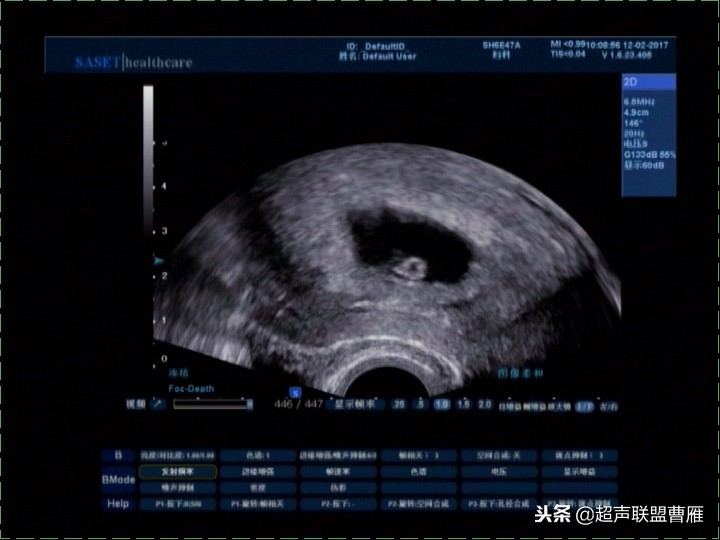

妊娠37天超声检查卵黄囊可以显示,羊膜腔及胚胎不能显示

真实的卵黄囊、胚体及羊膜腔形象

妊娠37天出现卵黄囊

在妊娠妊娠38天前后(36-40)天可以见到卵黄囊。 孕囊在6-9mm的可以见到其中有卵黄囊。